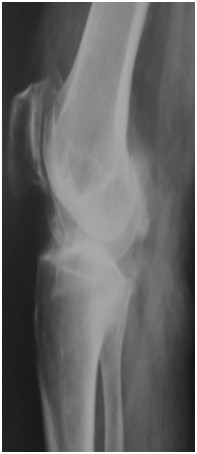

Приклад 1. Хвора Б. 52 років. Діагноз: Ревматоидній Деформівний IVст. гонартроз, вальгусна деформація колінногосуглоба.  Нестабільність та руйнування компонентів ендопротеза. Хворій виконано ревізійне ендопротезування: видалення компонентів ендопротезу, виявлений дефект латерального  виростку великогомілкової кістки тип Т3А за класифікацією АОRI [G.A. Engh, C.H. Rorabeck, 1997]. Під час операції виконана кісткова пластика дефекту латерального виростка лівої великогомілкової кістки. Використаний ендопротез колінного суглоба з подовжувачами .

Приклад 2. Хвора  М. 68 років. Діагноз: лівобічний деформівний IVст. гонартроз, стан після ТЕП лівого КС (2014р.). Під час виконання оперативного втручання компоненти ендопротезу встановлені в варусному положенні. Асептична нестабільність компонентів ендопротеза, тотальна  нестабільність зв’язкового апарату компонентів колінного суглоба (2017 р.)  Хворій виконано ревізійне ендопротезування: видалення компонентів ендопротезу, виявлений дефект виростку великогомілкової кістки тип Т2А за класифікацією АОRI [G.A. Engh, C.H. Rorabeck, 1997]. Враховуючи стан зв’язкового апарату використаний зв’язаний ендопротез типу Hinch.

Приклад 3. Хвора К. 52 років. Діагноз: Деформівний IVст. гонартроз, стан після ТЕП лівого КС (2013р.). ІМТ хворої складає 35 балів. Асептична нестабільність компонентів ендопротеза лівого колінного суглоба, міграція великогомілкового компоненту (2017 р.) (рис. 2 а). Хворій виконано ревізійне ендопротезування: видалення компонентів ендопротезу, виявлений дефект медіального виростку великогомілкової кістки тип Т3А за класифікацією АОRI [G.A. Engh, C.H. Rorabeck, 1997]. Під час операції виконана кісткова пластика дефекту. Використаний ендопротез колінного суглоба з подовжувачами.

Приклад 4. Хвора Г. 72 років. Діагноз: Деформівний IV ст. гонартроз, стан після ТЕП КС (2010р.). Гемартроз в післяопераційному періоді, хронічний синовііт.Септична нестабільність компонентів ендопротеза  колінного суглоба на протязі року. Виявлений дефект виростків стегнової кістки  тип Т3, F 3 за класифікацією АОRI [G.A. Engh, C.H. Rorabeck, 1997]. Хворій виконано  двоєтапне ревізійне ендопротезування: видалення компонентів ендопротезу іплантовано спейсер з антибіотиком. Піcля санаціїї виконано другий єтап певізії, імплантовано ревізійний ендопротез колінного суглоба.